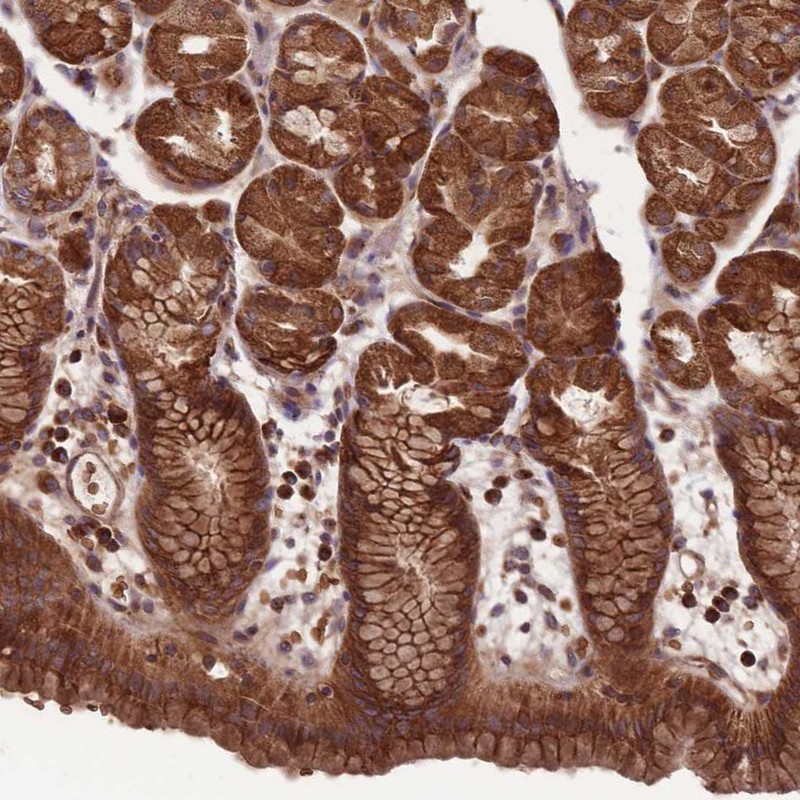

Immunohistochemical staining of human stomach shows cytoplasmic positivity in glandular cells.